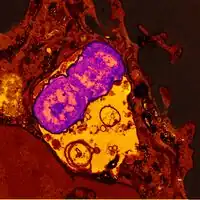

Human neutrophil containing ingested Klebsiella pneumoniae[15]

Mechanism

In terms of the pathophysiology of Klebsiella pneumonia we see neutrophil myeloperoxidase defense against K. pneumoniae. Oxidative inactivation of elastase is involved, while LBP helps transfer bacteria cell wall elements to the cells.[19][20]